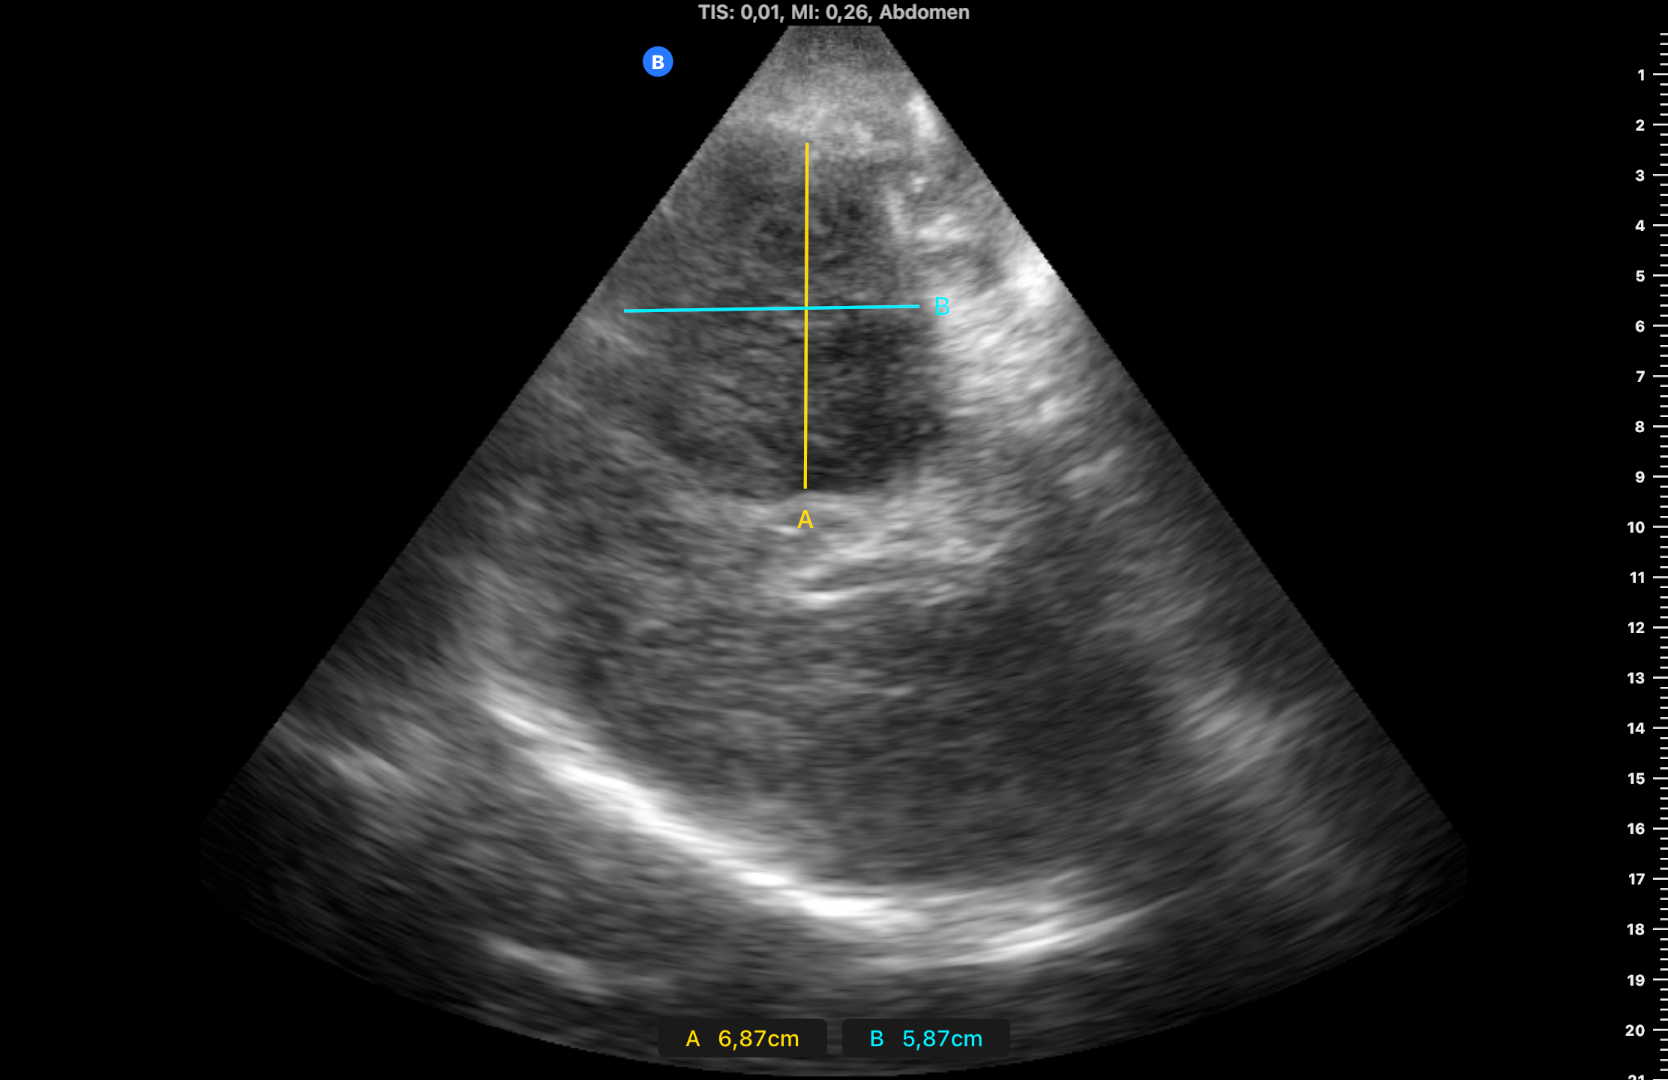

Ocupación de espacio con trombo venoso ecogénico desde poplítea hasta tercio superior, así como safenas externa e interna (imagen 2 femoral profunda e imagen 3 safena mayor). Lesión isoecogénica en segmentos hepáticos V/VI de 6,65 x 5,87 cm (imagen 4).

Masa hepática sospechosa de malignidad. TVP MID secundario a lo previo que se confirma por cirugía vascular. Diagnóstico diferencial con metástasis hepáticas y estirpe hepatobiliar.

En la analítica destaca CA 19-9 >12000 y en TAC body «masa hepática con signos de infiltración (hepatocarcinoma vs colangiocarcinoma) sin poder descartar metástasis». Eco BAG: compatible con neoplasia biliar.

Conclusiones y aplicabilidad para la medicina de familia

El diagnóstico final fue de colangiocarcinoma irresecable. El paciente fue tratado con quimioterapia. Fistulizó a ángulo hepático de colon y fundus vesicular. La TVP es uno de los escenarios más frecuentes en las consultas de Atención Primaria, observándose en muchas ocasiones neoplasias malignas subyacentes que desencadenan el cuadro. Una vez descartados los factores de riesgo asociados (inmovilización, trombopatías…) es fundamental descartar una etiología maligna. En este caso el diagnóstico etiológico se realizó desde el momento en que el paciente acudió a nuestra consulta, confirmándose días más tarde con técnicas de imagen avanzadas.